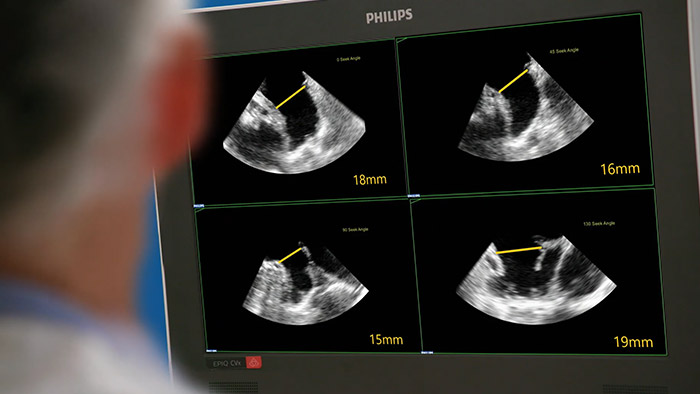

Schnelle, einfache und intuitive Beurteilung des linken Vorhofohrs. Die Philips Lösung für das linke Vorhofohr auf dem EPIQ CVxi.